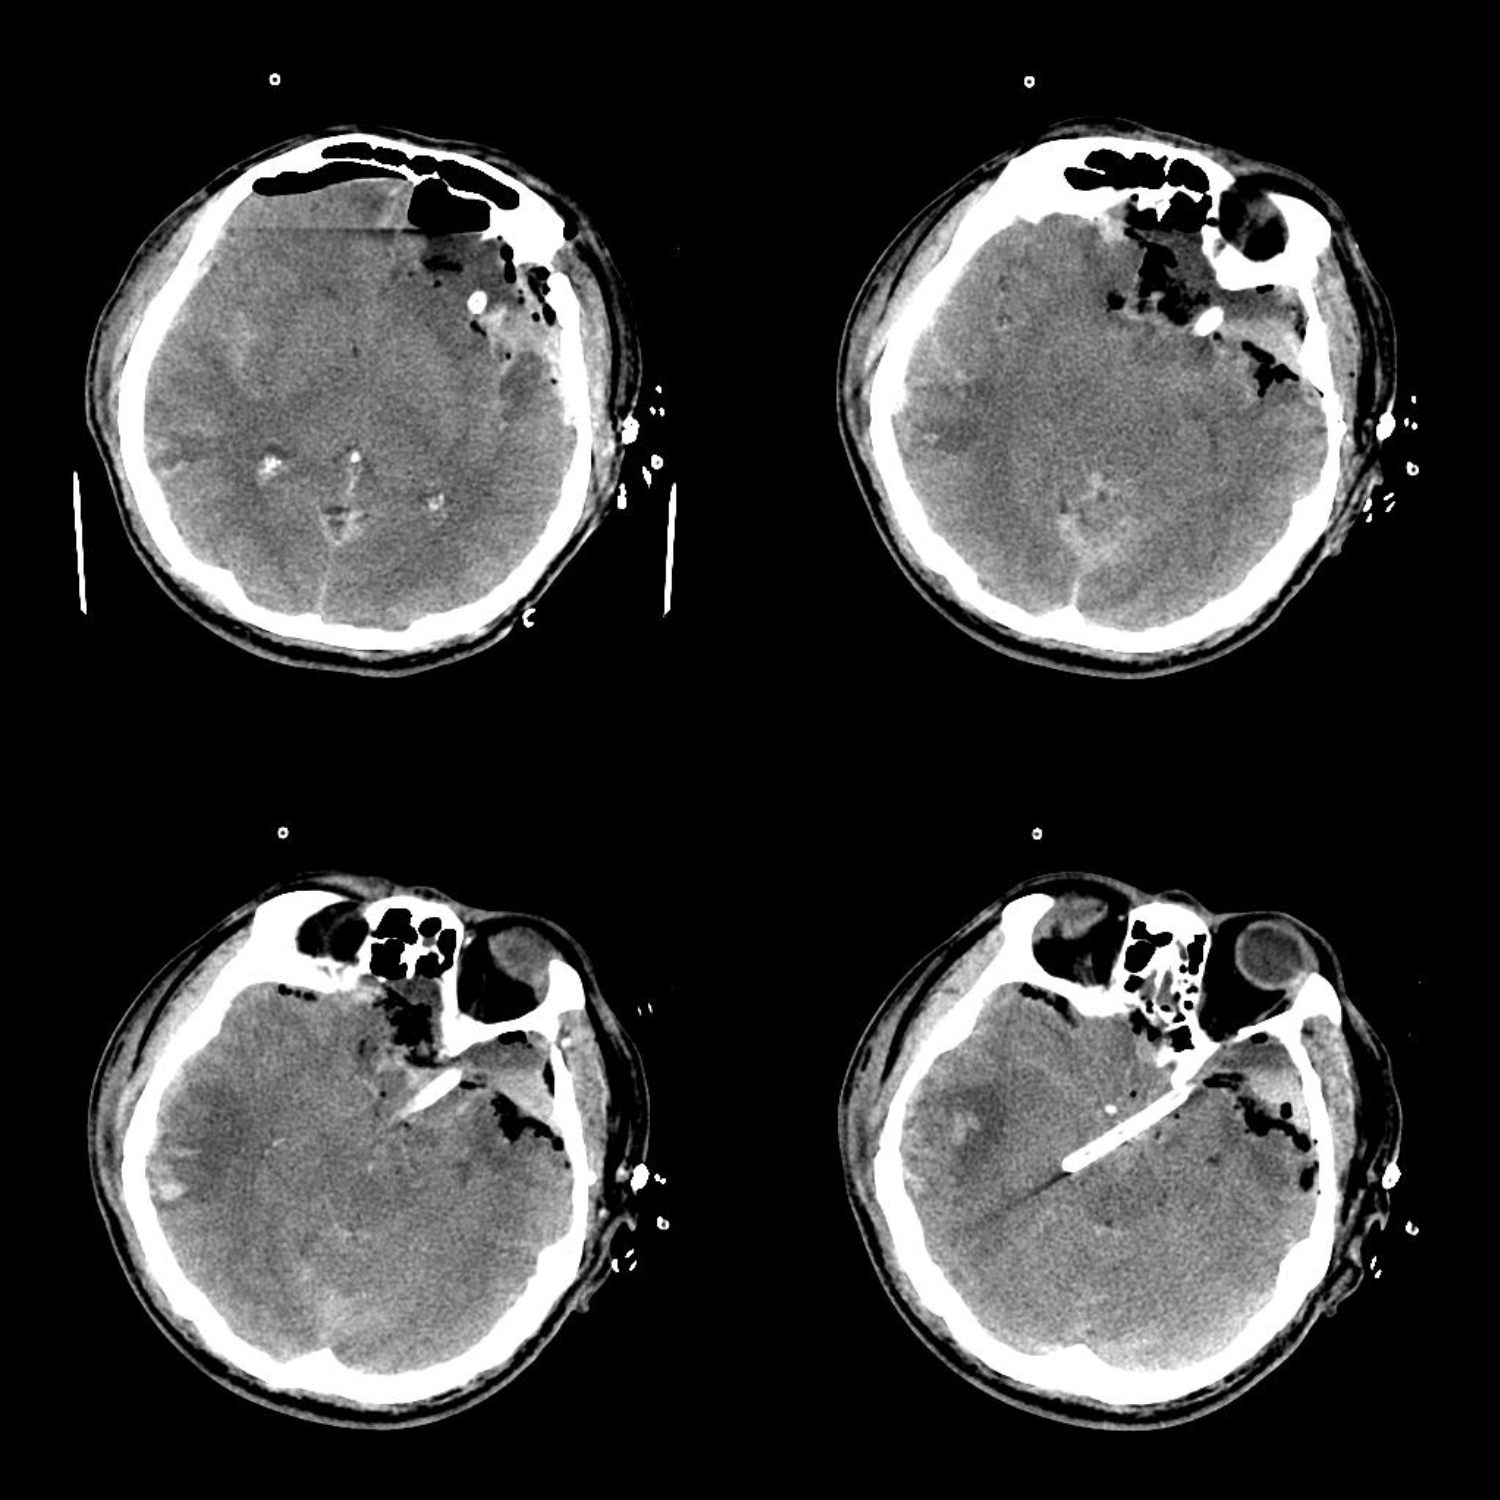

术后CT

术后患者颅压较高,脑池引流放置一周后予以拔除,患者神志转清,混合性失语,拟转康复科进一步康复治疗